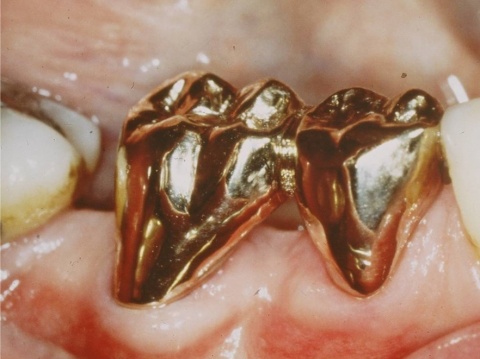

Ziel ist es, durch die Entfernung von Gewebs- und/oder Zahnanteilen die Zugänglichkeit zu schwer zugänglichen parodontalen Defekten zu verbessern. Darüber hinaus kann durch diese Maßnahmen die Hygienefähigkeit verbessert und eine Neubesiedelung des Parodontiums durch die mikrobielle Plaque verhindert werden. Vor allem die Prognose von furkationsbeteiligten Molaren kann auf diese Weise deutlich verbessert werden. In einer vielbeachteten Studie aus dem Jahre 2001 haben Fugazotto und Mitarbeiter die Prognose von 701 resektiv behandelten Molaren untersucht und beeindruckende Ergebnisse erzielt. Nach 15 Jahren waren noch 678 Molaren (94,9 %) in situ und erfüllten die vorgegebenen Erfolgskriterien. So lautete dann auch die Kernaussage dieser Studie, dass bei richtiger Indikationsstellung resektiv behandelte Molaren mindestens die gleich gute Langzeitprognose wie Implantate haben. In diesem Zusammenhang sei erwähnt, dass die Voraussetzung für eine erfolgreiche resektive Therapie die erfolgreiche endodontische Behandlung ist. Wie später noch ausgeführt wird, haben sich gerade auf diesem Gebiet durch technische Neuerungen völlig neue Möglichkeiten ergeben, was die Prognose der resektiv behandelten Molaren weiter verbessern dürfte. Ein kleines Beispiel, wie durch derartige Behandlungsschritte eine Implantation verhindert werden kann, zeigen die Abb. 5 und 6, wo durch eine Hemisektion des mesialen Wurzelanteils am Zahn 46 und anschließende Versorgung mit einer kleinen Brücke von 45 auf 46 eine Implantatinkorporation unnötig wurde.